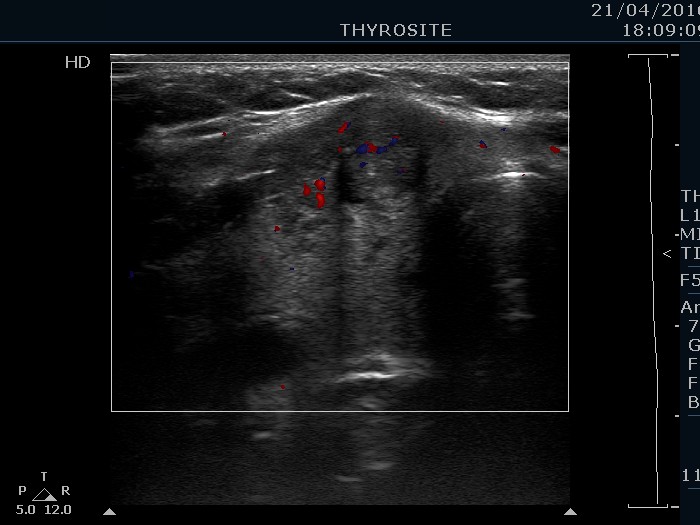

Right lobe, transverse scan, color Doppler mode. There are signs of intranodular blood flow.